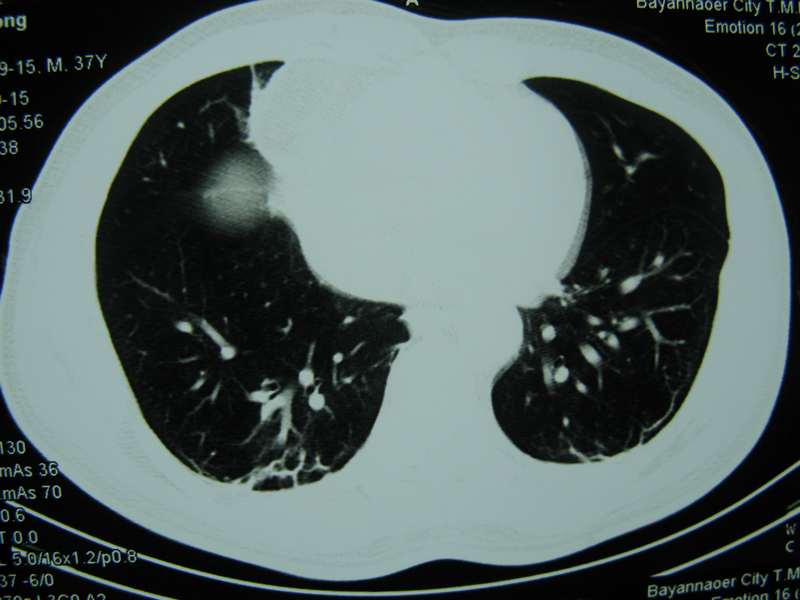

男,37岁,主述胸疼厉害,无咳嗽,无发热,血象也不高,病灶内ct值脂肪密度,右侧胸腔内少量积液,同道们考虑什么?谢谢!

脂肪垫,右下肺感染,少许积液是症状所在

纵膈脂肪堆积,右肺慢性炎症。

两肺下叶基底段纤维灶,右肺下叶基底背侧相应胸膜肥厚,右肺中叶内侧段部分不张。前中下纵隔团块状脂肪影,随访除外胸腺脂肪瘤。

纵膈脂肪堆积,右肺慢性炎症

脂肪垫;右肺慢性炎症。

不除外膈疝。